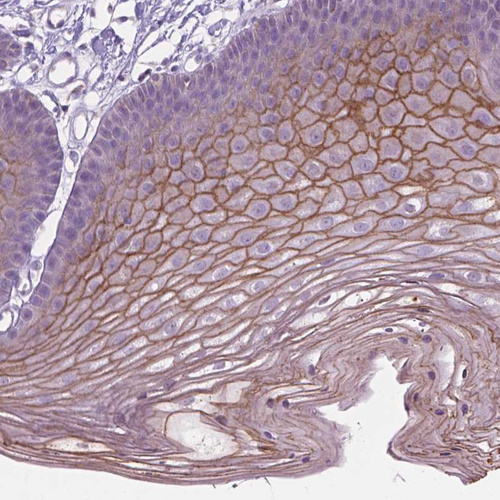

Immunohistochemistry analysis in human skin and kidney tissues using HPA062568 antibody. Corresponding SBSN RNA-seq data are presented for the same tissues.